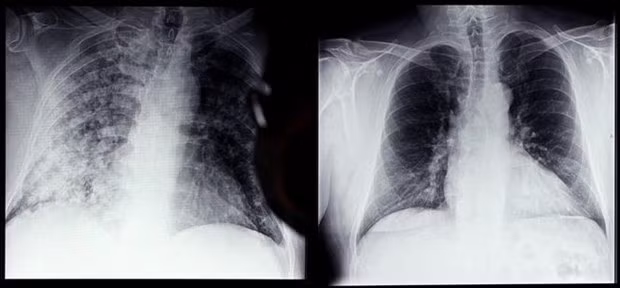

Phim chụp Xquang phổi của bệnh nhân COVID-19 (trái) và phổi của người bình thường tại bệnh viện ở Magdeburg, miền đông nước Đức, ngày 28/4/2021. (Ảnh: AFP/ TTXVN)